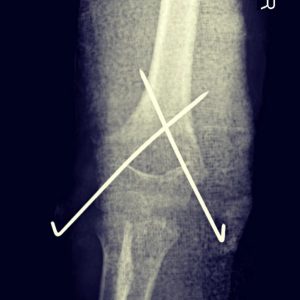

- Fracturas de codo

- Fractura supracondílea

Fractura supracondílea de humero